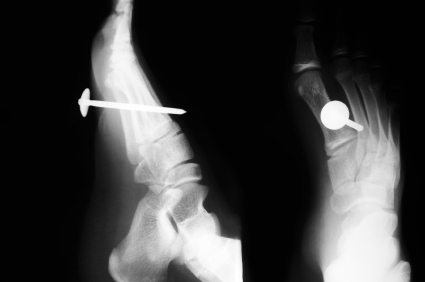

Chụp X-quang để loại trừ chấn thương xương hoặc để kiểm tra mảnh vỡ kim loại hoặc thủy tinh còn mắc lại ở vết thương.

Click vào ảnh để xem 4 hình ảnh minh họa